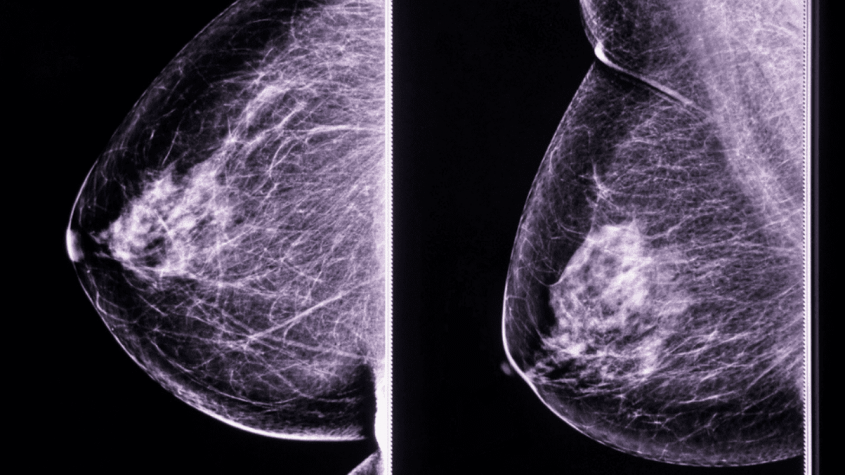

Este año, en el municipio de León se han efectuado 17,654 exploraciones clínicas de mama en mujeres mayores de 25 años en las unidades médicas jurisdiccionales, informó el secretario de Salud, Gabriel Cortés Alcalá. Asimismo, se realizaron 6,060 mastografías en el Hospital General de León y el Materno Infantil para detectar alteraciones sospechosas en etapas tempranas.

De esas acciones, 229 mujeres presentaron hallazgos sospechosos de malignidad clasificación BIRADS 4 y 5 y 52 casos fueron confirmados por la Secretaría de Salud local como cáncer de mama. La edad promedio de las pacientes es de 53 años, con un rango que va de 36 a 88 años.